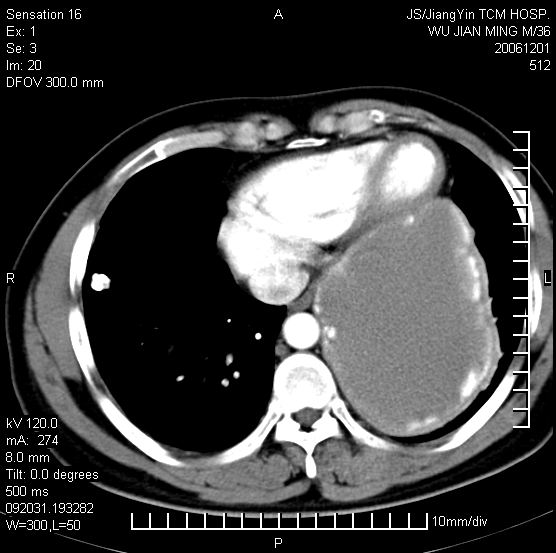

以下是引用dyqct在2006-12-1 21:17:00的发言:[br]左心缘旁及后肋膈窦区见巨大椭圆形混杂密度肿块,周围见大小不等斑片状钙化,内部无强化,周围包膜轻度强化,心脏明显受压变形,即明显占位效应,肿块广基与心包、膈相连。肝、脾内、肝门见多数小结节状钙化影。[br]考虑:1、左心缘旁及后肋膈窦区慢性包裹性胸膜炎(结核性);[br] 2、肝、脾及肝门淋巴结核已钙化。[br]

以下是引用zrs在2006-12-2 17:28:00的发言:[br]肺内、肝脾内虽有钙化,但不支持结核性胸胸膜炎包裹,而支持寄生虫感染![br][br]

以下是引用zyx168在2006-12-2 10:10:00的发言:[br][br]肝脾肺内多发钙化灶